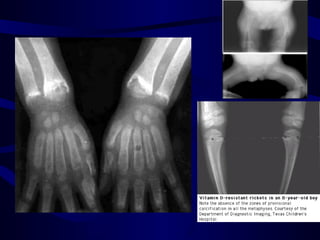

Rickets

• Rickets is a softening of the bone due to

deficient mineralization at the growth plate.

• It is common in children and is potentially

leading to fractures and deformity.

• Rickets is among the most frequent childhood

diseases in many developing countries. The

predominant cause is a vitamin D deficiency,

but lack of adequate calcium in the diet may

also lead to rickets.

• EXTREMITIES

– Enlargement of wrists and ankles;

– Valgus or varus deformities

– Bowing of the tibia and femur;